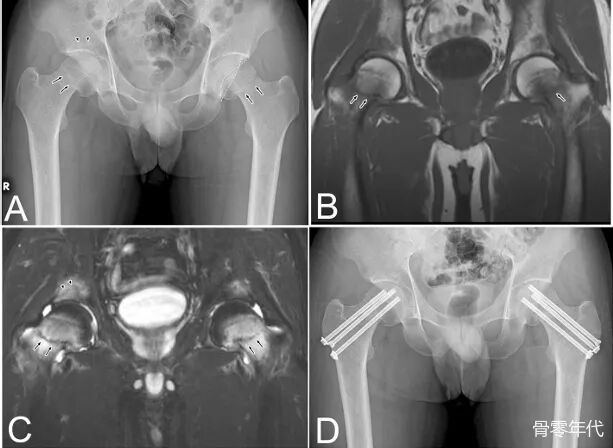

一名33岁男性因双侧腹股沟不适就诊,该症状于两周前开始。X光片显示双侧股骨颈骨折,此外,磁共振成像(MRI)发现右侧髋臼下软骨区存在骨折线。尽管患者没有明显的骨质疏松相关危险因素,但通过双能X线吸收法测得的骨密度显示严重骨质疏松(腰椎:T值−3.4标准差[SD];股骨颈:T值−2.8 SD)。血清25-羟维生素D水平不足(19 ng/mL),部分原因被认为是因为社交退缩导致3年来缺乏阳光照射。考虑到其年轻年龄,尽管骨折发生已超过两周,仍进行了双侧骨折内固定术。术后8个月的X光片和MRI确认骨折愈合良好,股骨头未发生骨坏死。